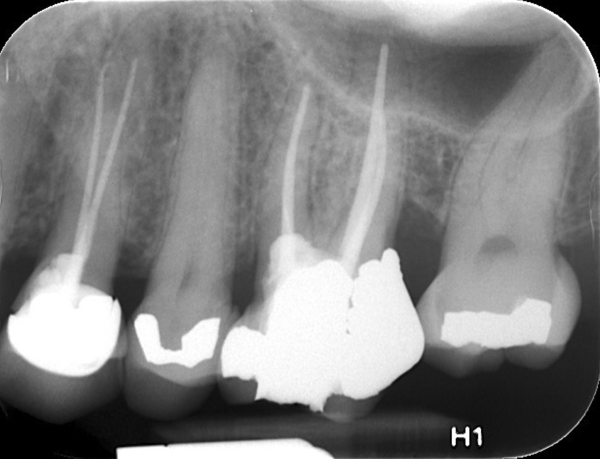

Fig 13. 2-year follow-up radiographs showing the positive outcome.

Figure 13

Fig 14. 2-year follow-up radiographs showing the positive outcome.

Figure 14

Clinical procedure: Once a perforation occurs, the extent of the perforation must be assessed. If there is an adjacent bony defect, the bony defect should first be filled with an osteoconductive or osteoinductive material. This can be done with a bone graft, calcium sulfate, or collagen/gelatin sponge. The dentinal portion of the tooth that has been perforated is then restored with MTA (Figure 9 through Figure 14).